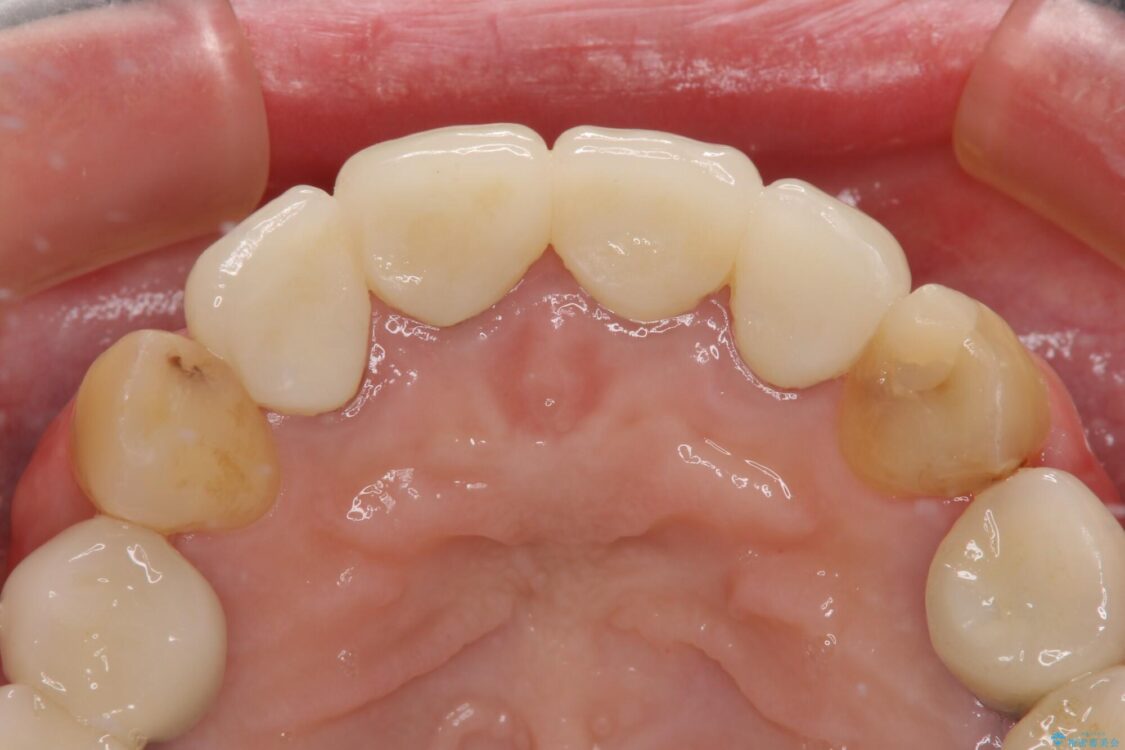

治療前

• 仮歯のまま放置した前歯 オールセラミッククラウンで自然な前歯に 治療前画像

仮歯装着後に放置してしまい、恥ずかしいとのことで来院された患者様です。

仮歯が不適合で歯肉が腫脹していたため、しっかりと調整した新しい仮歯にして腫れを改善した上で、オールセラミッククラウンにて補綴することとしました。